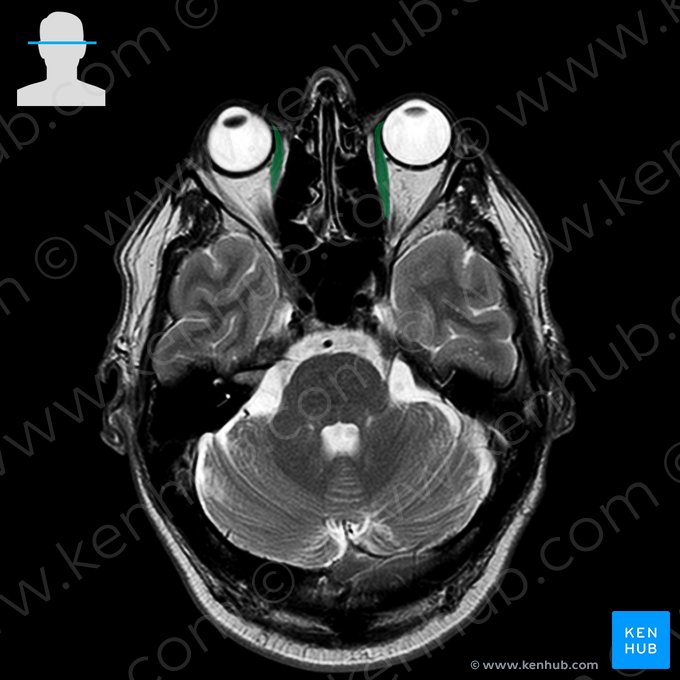

Medial rectus muscle

Medial rectus is one of the six extraocular muscles located in the orbit. Attaching between the bony walls of the orbit and the eyeball, these muscles serve to synchronously move the eyes. Besides medial rectus, this group of muscles also gathers the superior rectus, inferior rectus, lateral rectus, superior oblique and inferior oblique muscles. Notice how these muscles are divided into four recti and two oblique muscles. The former move the eyes in the four cardinal directions, while the latter adjust the position of the eyeball depending on the position of the head.

Like the other recti muscles, medial rectus arises from a connective tissue ring located at the apex of orbit, called the common tendinous ring (anulus of Zinn). The muscle attaches to the medial side of anterior half of eyeball, therefore adducting the eyeball when contracting.

The muscle courses anteriorly, sliding over the medial part of the eye to cross its equator and reach the anterior half of the eyeball. It then inserts onto the medial side of the eyeball, around 5 millimeters posterior to corneoscleral junction. The inserting muscle fibers pierce the fascial sheath of the eyeball (Tenon’s capsule), which in turn reflects back and creates a thin fascial sleeve around the muscle’s tendon. This sleeve gives off an expansion called the medial check ligament that connects the medial rectus muscle with the medial wall of orbit.

Medial rectus muscle runs cushioned in the periorbital fat tissue, superior to the floor of the orbit and inferior to the superior oblique muscle, ophthalmic artery and nasociliary nerve. The lateral surface of this muscle encloses a triangular space with the posteromedial surface of the eye and optic nerve. The inferior branch of the oculomotor nerve traverses this space in order to reach and penetrate the lateral surface of the muscle.